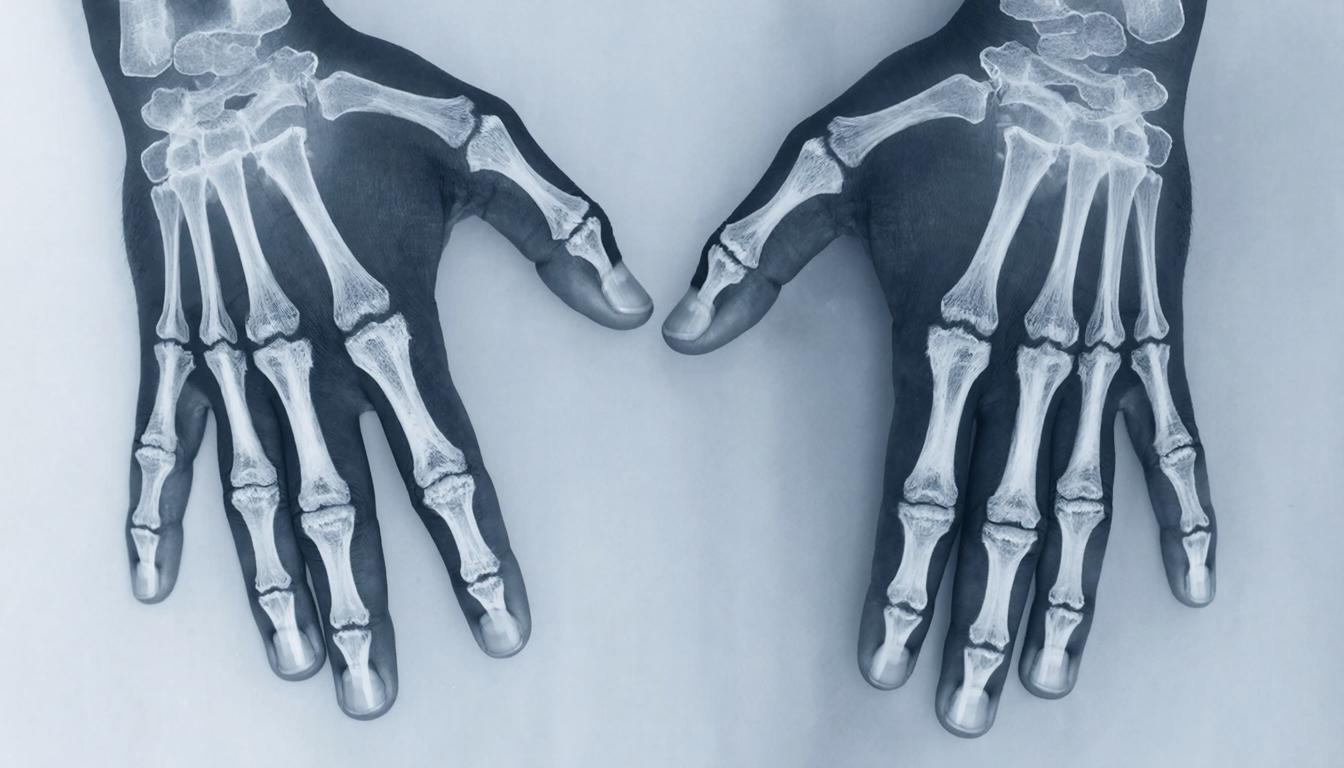

Рентгенография — это один из самых распространенных и доступных методов диагностики, который помогает врачам получить визуальную информацию о состоянии внутренних органов и тканей пациента.

Рентгенография — это метод визуализации, основанный на использовании рентгеновских лучей, который позволяет получить изображения внутренних структур организма (уточнить форму органов, их положение, тонус, перистальтику, состояние слизистой оболочки). Рентген это плоское изображение трехмерного объекта. Процедура быстрая, не требует сложной подготовки и обычно занимает всего несколько минут.

Рентген суставов;

-

Рентгенография кисти (2 кисти в прямой проекции)

2 000 ₽

Рентгенография кисти

1 700 ₽